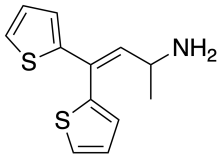

The pharmacodynamic response to an opioid depends upon the receptor to which it binds, its affinity for that receptor, and whether the opioid is an agonist or an antagonist. For example, the supraspinal analgesic properties of the opioid agonist morphine are mediated by activation of the μ1 receptor; respiratory depression and physical dependence by the μ2 receptor; and sedation and spinal analgesia by the κ receptor. Each group of opioid receptors elicits a distinct set of neurological responses, with the receptor subtypes (such as μ1 and μ2 for example) providing even more [measurably] specific responses. Unique to each opioid is its distinct binding affinity to the various classes of opioid receptors (e.g. the μ, κ, and δ opioid receptors are activated at different magnitudes according to the specific receptor binding affinities of the opioid). For example, the opiate alkaloid morphine exhibits high-affinity binding to the μ-opioid receptor, while ketazocine exhibits high affinity to ĸ receptors. It is this combinatorial mechanism that allows for such a wide class of opioids and molecular designs to exist, each with its own unique effect profile. Their individual molecular structure is also responsible for their different duration of action, whereby metabolic breakdown (such as N-dealkylation) is responsible for opioid metabolism.

There are a number of broad classes of opioids:[260]

Tramadol and tapentadol, which act as monoamine uptake inhibitors also act as mild and potent agonists (respectively) of the μ-opioid receptor.[264] Both drugs produce analgesia even when naloxone, an opioid antagonist, is administered.[265]